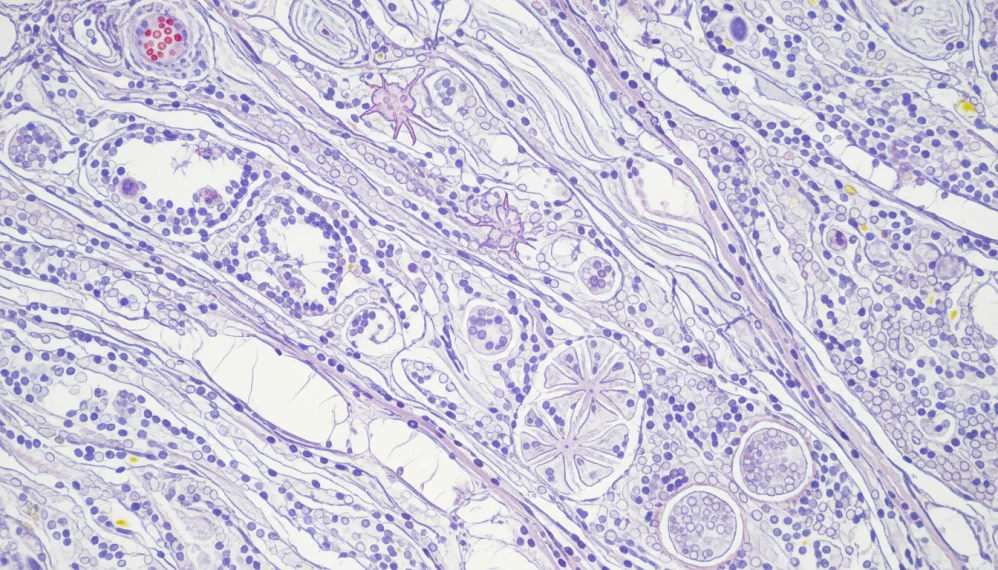

Tesutul conjunctiv este materialul care mentine impreuna celulele vii din interiorul corpului.

Acesta este lipiciul celular care le ofera tesuturilor forma, contribuie la rezistenta lor si sustine functia acestora.

Cartilajul si grasimea sunt exemple de testut conjunctiv.

Tulburarile tesutului conjunctiv pot provoca inflamatia osului, a grasimii, cartilajelor, tendoanelor, ligamentelor si pielii si ar putea rezulta multiple simptome.